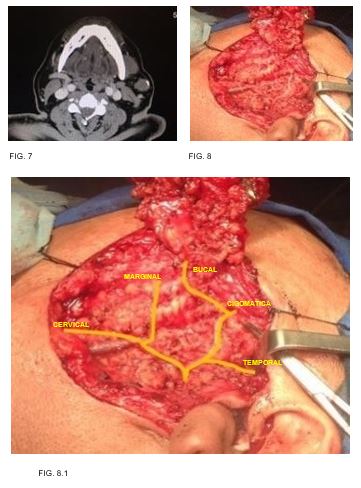

Caso 4: masculino 56 años de edad, antecedente de diabetes mellitus, tabaquismo e hiperplasia prostática, con tumor parotídeo izquierdo de 3cm en su eje mayor, resultando en adenoma pleomorfo. (FIG. 7-8)

Las ramas temporales del nervio facial se encuentran anteroinferior a la arteria superficial temporal, por lo que resulta en un punto de referencia importante para preservar la rama temporal. La rama cigomática transcurrió en todos los casos debajo y paralelo al arco cigomático hasta llegar a la parte inferior del músculo orbicular. La rama bucal corre paralela al conducto parotídeo hacia el músculo buccinador. El origen de la rama bucal ha sido reportada como la más variable de las ramas faciales terminales, por lo tanto, se ha utilizado por algunos autores para clasificar el nervio facial en diferentes patrones de ramificación (Katz y Catalano, 1987;

kwak et al., 2004). 3 Dentro de nuestra descripción encontramos

su origen con mayor frecuencia en el tronco temporofacial (n=5, 50%), en otros tres nervios surgió del tronco cervicofacial (30%) y en una minoría presentó un origen como una raíz doble de ambas divisiones que se unen para formar una sola rama bucal (n=2, 20%). la rama marginal pasa sobre la arteria facial cuando cruza el límite inferior de la mandíbula, en los diez casos se encontró una rama única. En nuestros pacientes, como se menciona en la literatura, se tomaron en cuenta las principales referencias anatómicas como lo son la apófisis vaginal del cartílago tragal, la cual presento distancia promedio de 8.2mm, encontrando un caso en el que este se encontraba a tan solo 6mm del pointer y otros mas en los que la distancia era del doble de esta última mencionada, por lo que esta variabilidad obliga a tomar en cuenta otras referencias importantes en la ubicación del nervio, además de las clásicas, como lo es la apófisis estiloides así como la punta de la mastoides, las cuales invariablemente permiten localizar de forma confiable y segura la salida del NERVIO FACIAL A SU SALIDA DEL agujero estilomastoideo.